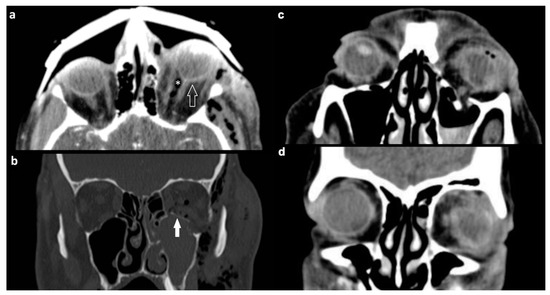

| Orbital vessels | 16 (15.8) | |

| dilated superior ophthalmic vein | 10 (9.9) | |

| direct carotid cavernous fistula | 6 (5.9) |